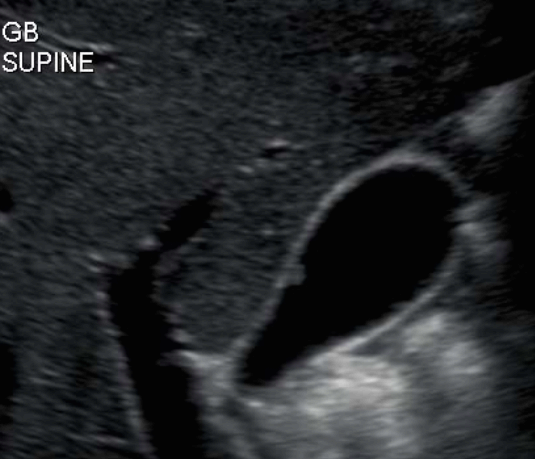

담낭 용종 ( GB polyp ) 담낭 안쪽 벽에서 담낭 안으로 돌출된 다양한 형태의 점막이 두꺼워진 것이다. 용종 자체로는 큰 문제를 일으키지 않으나, 용종의 크기가 커지면 암으로 변할 가능성이 높다. 용종의 크기가 직경 10mm 이상인경우 악성일 가능성이 높다.

발생빈도는 성인의 약 3~7% 정도이고 남성보다는 여성에서 2배 정도로 많으며 40대에서 많이 발생한다. 증상이 없으며 우연히 발견되나 드물게 명치끝이나 우상복부에 통증을 호소하는 경우도 있다.

1cm 이상의 담낭 용종은 수술로 담낭 전체를 제거하는 것을 원칙으로 하고, 1cm 미만인 경우는 주기적인 추적관찰을 한다. 용종의 크기가 1cm 미만이라 하더라도 담석이 동반되어 있거나, 증상( 복통, 담낭염등)이 있는 경우는 제거하는 것이 좋다.

1. 콜레스테롤 용종 (cholesterol polyp) : 50~90%로 가장 흔한 타입

- 1cm 미만의 고에코의 종괴 (hyperechoic mass) : 담석에 비해 에코가 낮고, 담낭벽보다는 고에코로 보임

- 담낭벽에 붙어 체위변화 시 이동이 없다

- 후방음영이 없다